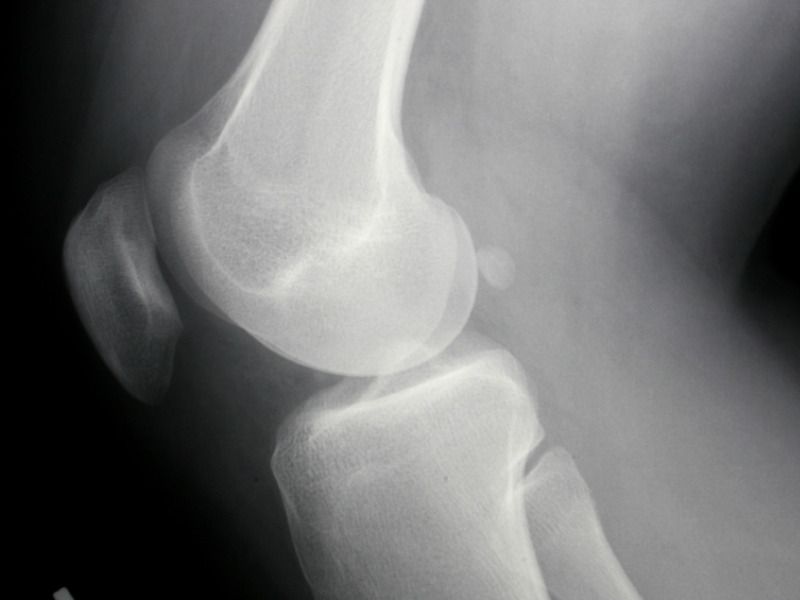

Одно из крупнейших исследований, проведенное в 2006 году, включало более 1,500 участников с остеоартритом коленного сустава. В этом исследовании участникам давали либо глюкозамин, либо хондроитин, либо комбинацию этих веществ. Результаты показали, что комбинация глюкозамина и хондроитина значительно уменьшала боль и улучшала функцию суставов по сравнению с плацебо. Однако, в некоторых случаях эффект был более заметен у тех, кто принимал только глюкозамин.